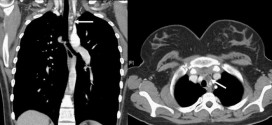

CANCER DE ESOFAGO DISTAL

El cáncer de esófago distal. El esófago es un tubo muscular, hueco, que se extiende desde la faringe hasta el estómago, y sirve para el paso de alimento. En su recorrido, atravesando el cuello y el tórax para llegar al abdomen, se encuentra por delante de la columna vertebral, en íntima relación con distintas estructuras (aorta, nervio recurrente laríngeo izquierdo, …